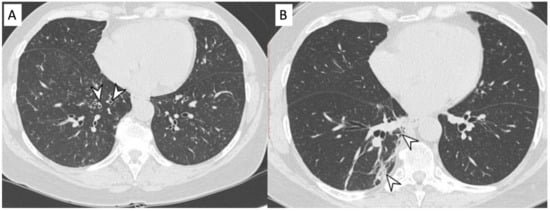

2.4. Granulomatosis with Polyangiitis (GPA-Wegener’s Disease)

| GPA | Solid nodules, GGOs due to hemorrhagic alveolitis (common); halo sign, crazy paving (less common) |